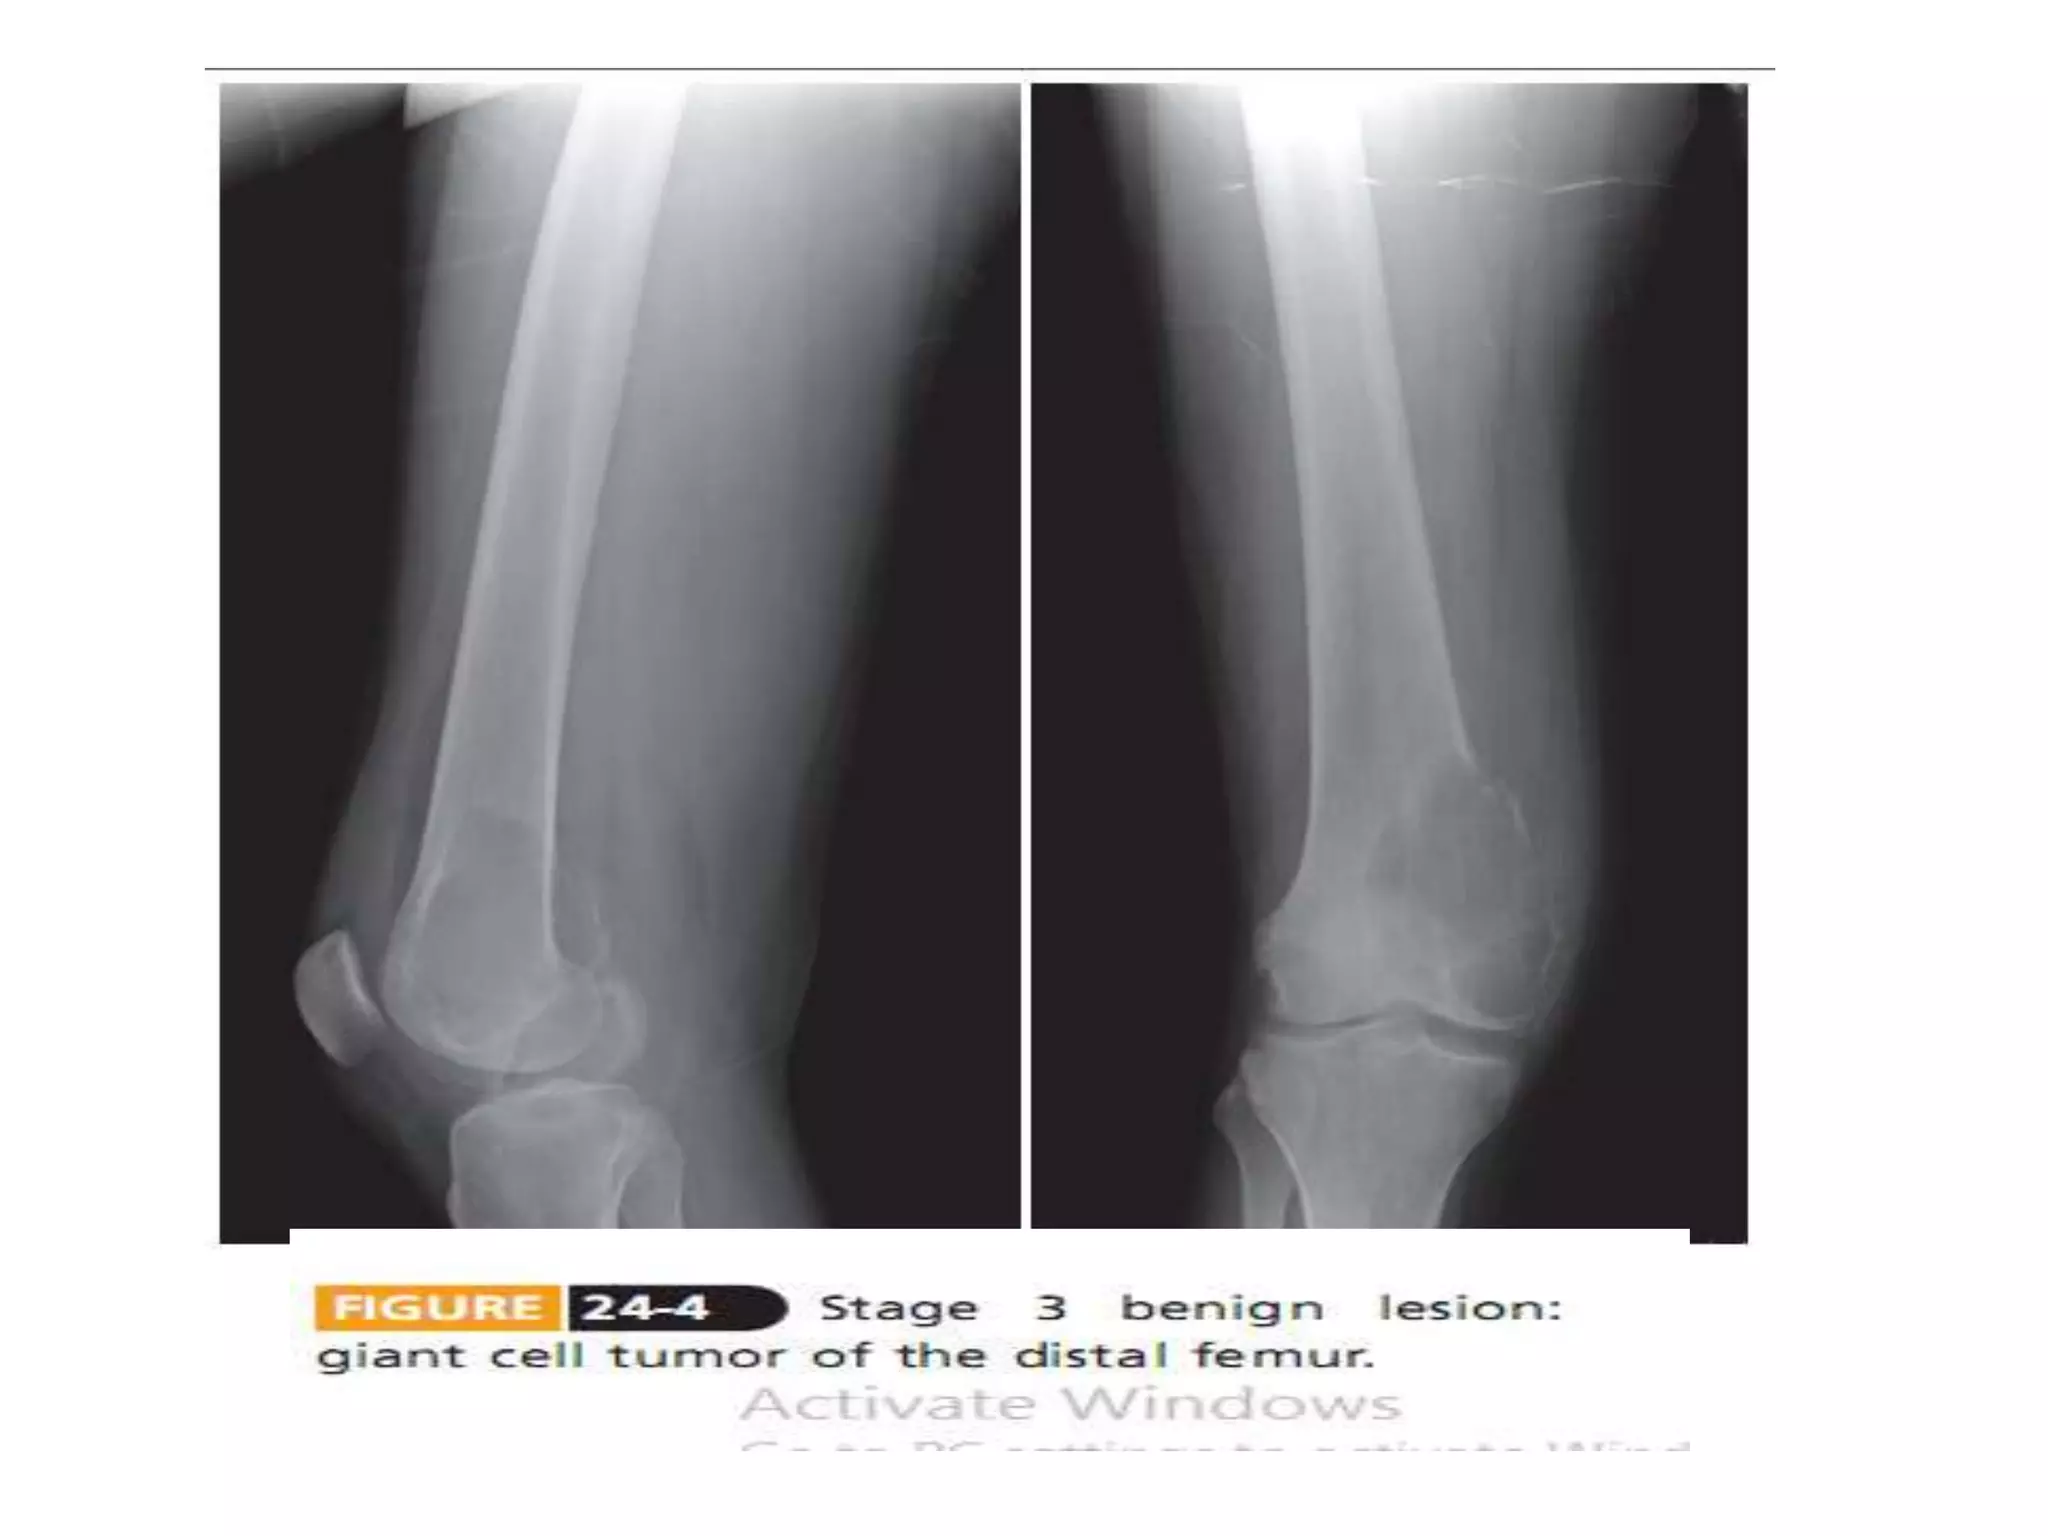

ANEURYSMAL BONE CYST

• Locally destructive, blood-filled reactive lesions of bone

• Slight female predominance

• Common sites – proximal humerus, distal femur, proximal

tibia, and spine

• Clinical features

– mild to moderate pain

– rapid growth – mimics malignancy

– spinal lesions – neurological deficits or radicular pain

• Plain Radiography

– Expansile, eccentrically located lytic lesion -

metaphyses, elevated periosteum +/- periosteal

reaction, lined by thin shell of cortical bone

• Bone scan

– diffuse or peripheral tracer uptake with central area

of decreased uptake

Treatment

Extended curettage and grafting with a bone graft

substitute under tourniquet control

Marginal resection – rarely

Spine or pelvis lesions – preoperative embolization

Arterial embolization – difficult locations

Low-dose irradiation - effective method, not used

routinely – risked malignant transformation